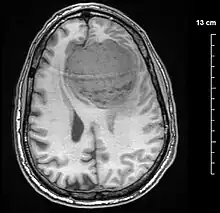

![]() | |

A contrast-enhanced CT scan of the brain, demonstrating the appearance of a meningioma | |

Meningiomas are visualized readily with contrast CT, MRI with gadolinium,[22] and arteriography, all attributed to the fact that meningiomas are extra-axial and vascularized. CSF protein levels are usually found to be elevated when lumbar puncture is used to obtain spinal fluid. On T1-weighted contrast-enhanced MRI, they may show a typical dural tail sign absent in some rare forms of meningiomas.[17]